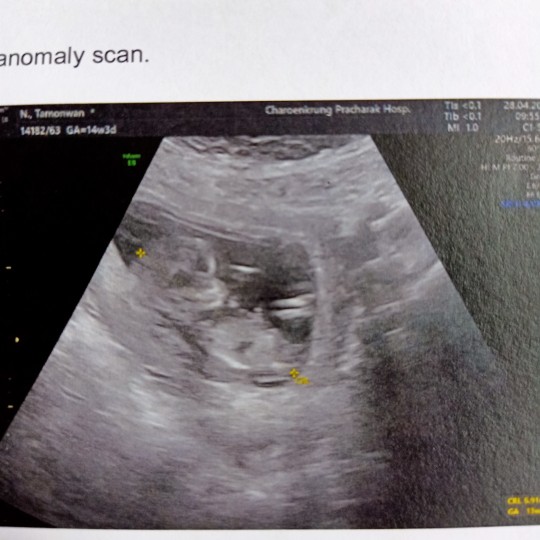

14w3dคะ